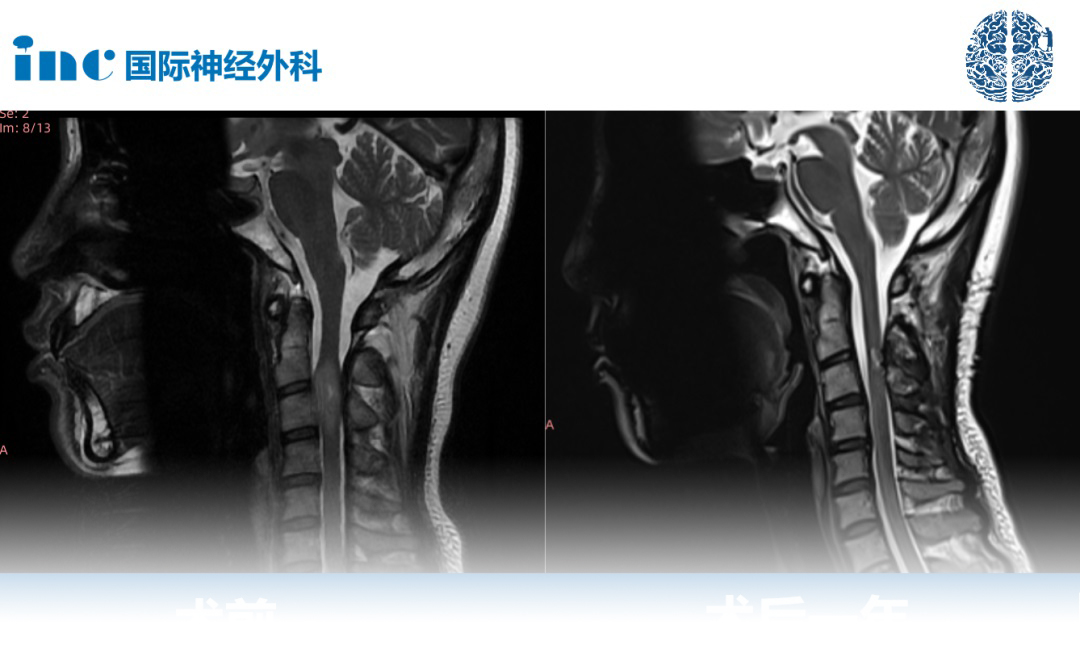

2021年7月行增强磁共振提示C3水平占位,直径7mm。当地医院排除炎性病变。因考虑到手术风险大,未作手术治疗。

2022年6月磁共振提示大小约8*12*14mm。2022年10月磁共振提示8*12*19mm。虽然这颗颈髓内的肿瘤仅仅只有1cm左右花生大小的肿瘤,但是伴随而来的症状越发严重,除了手臂、指尖、腿部等肢体麻木、接踵而来的背部疼痛让她夜不能寐,正处盛年的她笼罩在病魔的阴影之下。肿瘤持续进展,年轻的潇潇不愿意继续坐以待毙。